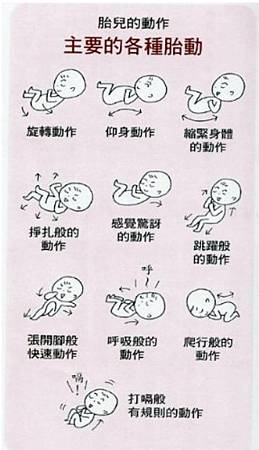

胎动有快有慢 时强时弱 可能是胎宝宝在肚子里做这件事呢 胎儿

胎動 時寶寶在肚裡是這樣 醫影片告訴你一天可動幾百次 Ettoday健康雲 Ettoday新聞雲

有頻率的胎動 愛淘生活